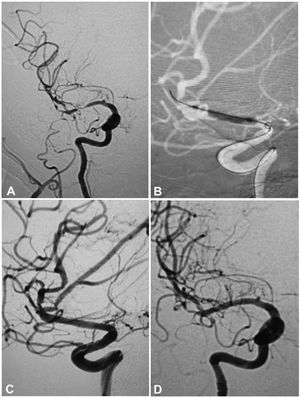

A 53-year-old woman had an atherosclerotic stenosis (78%) at the M1 segment of the right middle cerebral artery (MCA) treated with the angioplasty and stenting of the Low-Profile Visualized Intraluminal Support (LVIS) stent. (A) The stenosis was shown at the M1 segment. (B) A balloon was used to dilate the stenosis before stenting. (C) At the end of the stenting with a LVIS stent (3.5mm×15mm), the stenotic segment was restored to the normal diameter. (D) At 12-month follow-up, the stented segment of artery remained totally open with no instent stenosis.